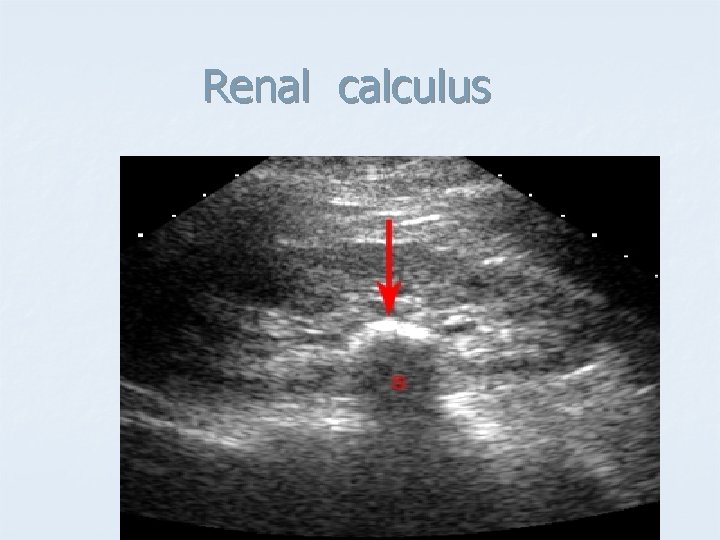

Renal calculus